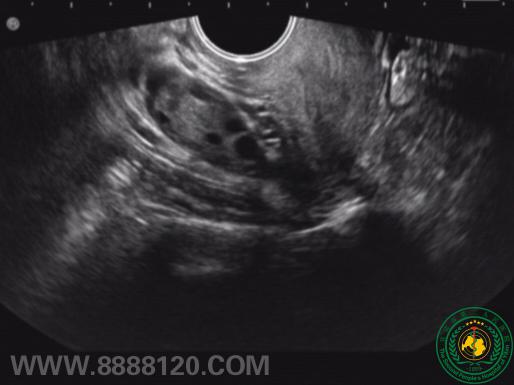

活泼过头的附件

活泼过头的附件  52426

宜宾市第二人民医院 图文